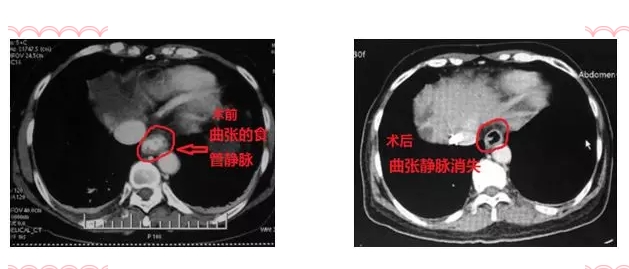

术后7天,患者再次出现上消化道出血,行造影检查,患者胃冠状静脉栓塞良好,未见明显出血血管,只能使出最后杀手锏—TIPS(经颈静脉肝内门体分流术),术后患者出血停止,康复出院。

朱亮副主任医师表示:其实解决门静脉压力高的问题,就像大禹治水一样,光堵是不行的,堵永远不如疏!“隧道工程”是TIPS手术的关键技术点:在肝静脉、门静脉之间建立“隧道”,部分门静脉血流直接进入肝静脉,降低了门静脉压力,门体压力梯度降低了,出血自然停止了。